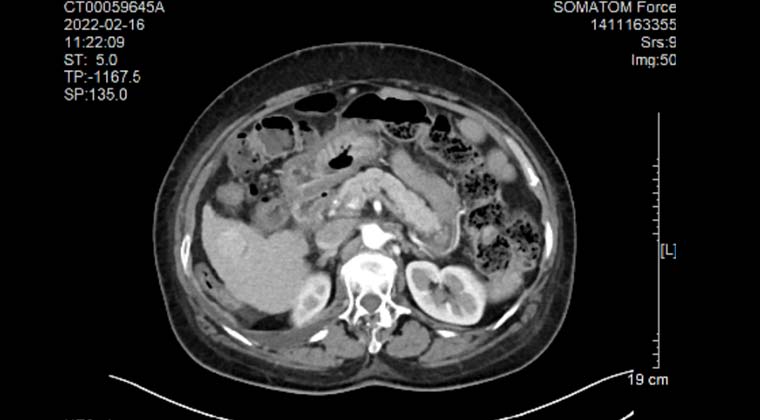

Пациент: женщина, 70 лет, злокачественная солидная опухоль печени, очаг расположен рядом с кишечником.

Процедура: выполнена под общим наркозом. Через чрескожный прокол были размещены два электрода, охватывающие очаг, после чего проведена абляция. Во время процедуры сила поля оставалась стабильной, ток заметно увеличился, абляция прошла успешно.

После процедуры: на контрольной КТ с контрастированием границы очага четкие, зона абляции без выраженного усиления.

КТ с контрастированием перед процедурой